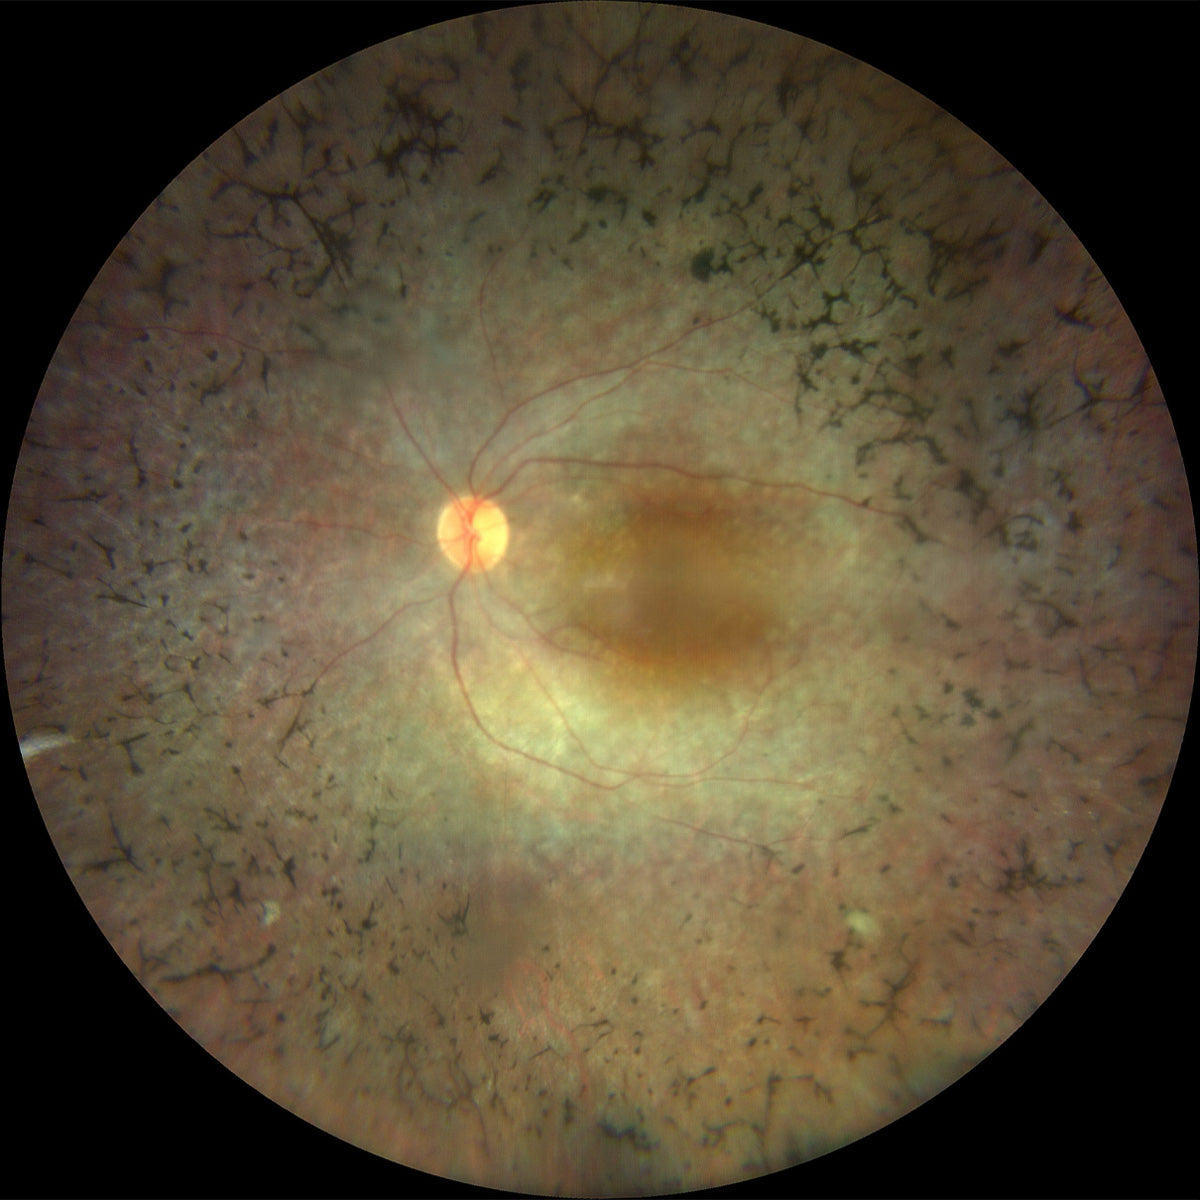

La Retinite Pigmentosa (spesso chiamata anche Retinite Pigmentosa) è una malattia oculare degenerativa che coinvolge la retina e, in particolare, i fotorecettori responsabili della visione notturna e periferica. Si tratta di una patologia genetica e progressiva, che nel tempo può determinare un restringimento del campo visivo, alterazioni della percezione luminosa e una significativa difficoltà nella visione in condizioni di scarsa illuminazione.

La malattia colpisce prima i bastoncelli (responsabili della visione periferica e crepuscolare) e, in fasi successive, può coinvolgere anche i coni, compromettendo anche la visione centrale e dei colori.